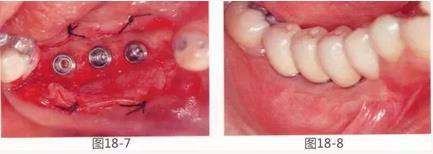

360截圖20170422142129245.jpg

圖18-7  將種植體埋入后的狀態(tài)。

圖18-8  術(shù)后1年6個(gè)月。配裝上部結(jié)構(gòu)時(shí)的狀態(tài)。